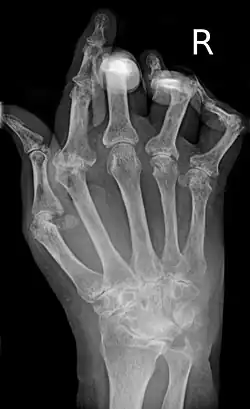

As the pathology progresses, the inflammatory activity leads to tendon tethering and erosion and destruction of the joint surface, which impairs range of movement and leads to deformity. The fingers may develop almost any deformity depending on which joints are most involved. Specific deformities, which also occur in osteoarthritis, include ulnar deviation, boutonniere deformity (also "buttonhole deformity", flexion of proximal interphalangeal joint and extension of distal interphalangeal joint of the hand), swan neck deformity (hyperextension at proximal interphalangeal joint and flexion at distal interphalangeal joint) and "Z-thumb." "Z-thumb" or "Z-deformity" consists of hyperextension of the interphalangeal joint, fixed flexion, and subluxation of the metacarpophalangeal joint and gives a "Z" appearance to the thumb.[16]: 1098 The hammer toe deformity may be seen. In the worst case, joints are known as arthritis mutilans due to the mutilating nature of the deformities.[20]

X-rays of the hands and feet are generally performed when many joints are affected. In RA, there may be no changes in the early stages of the disease, or the X-ray may show osteopenia near the joint, soft tissue swelling, and a smaller than normal joint space. As the disease advances, there may be bony erosions and subluxation. Other medical imaging techniques such as magnetic resonance imaging (MRI) and ultrasound are also used in RA.[20][79]